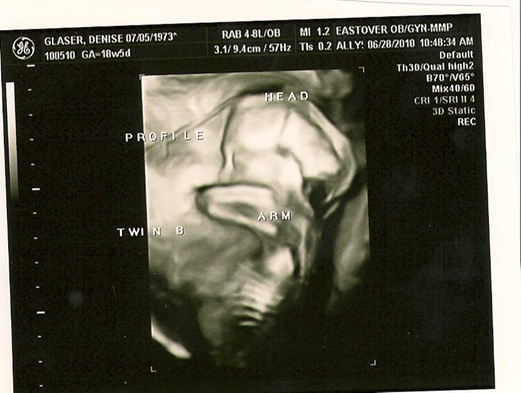

First – a look back at their 20 week ultrasound (when we discovered they were boys).  There are little labels on the pictures written by the technician, but don’t be worried if you can’t really tell what’s what… you get the general idea…

no, he doesn’t have a hole in the side/back of his head – it’s just how the 4D picture is taken.  arm is up and he’s totally chillin’.